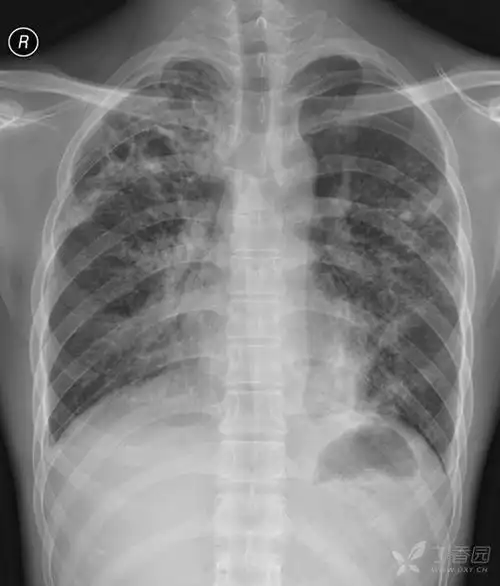

初步诊断 急性粟粒型肺结核.